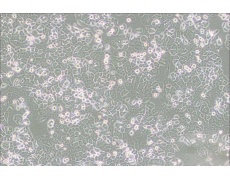

NCI-H2126人肺癌細胞

中文名稱 : 人肺癌細胞

細胞簡稱 : N CI-H 2126

細胞形態(tài) : 上皮細胞樣

生長特性 : 貼壁細胞